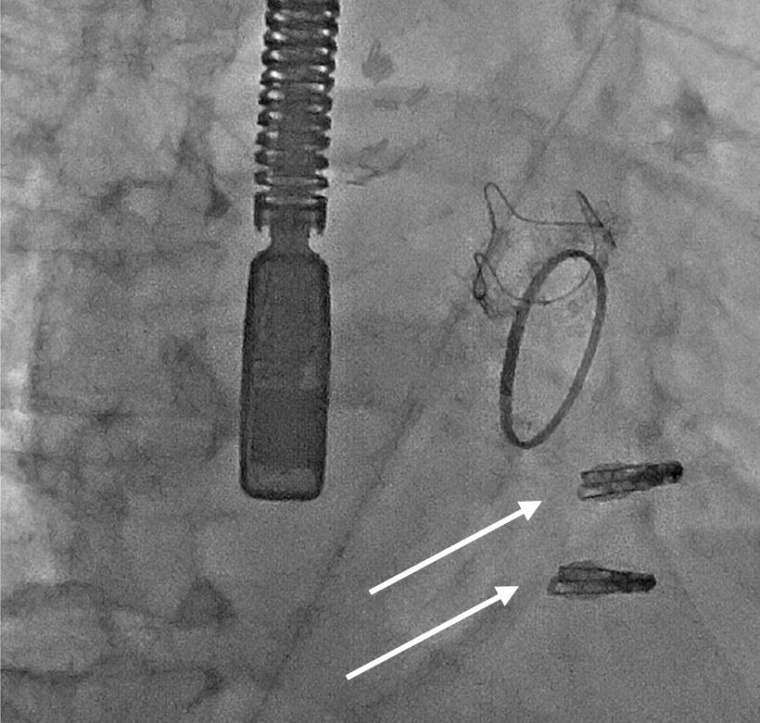

Bei der nun vorgenommenen Trikuspidalklappenreparatur werden Trikuspidalklappen-Clips implantiert. Die Clips halten die Klappensegel zusammen und sorgen dafür, dass diese wieder dicht abschließen. Chefarzt Prof. Dr. Marc Horlitz ist von diesem Verfahren überzeugt. „Wir haben die Herzklappenreparatur mit den Clips im letzten Jahr bereits bei der Mitralklappe angewandt und sind von den Erfolgen begeistert. Die schonende Katheterbehandlung von Herzklappen ermöglicht es uns, PatientInnen zu behandeln, denen bisher nicht geholfen werden konnte.“